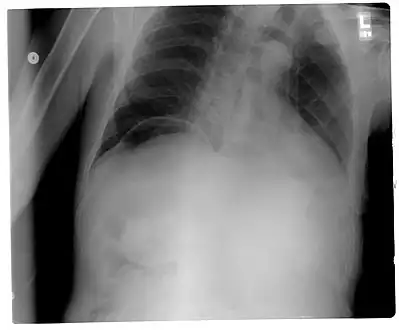

Another pneumoperitoneum on chest X-ray. -